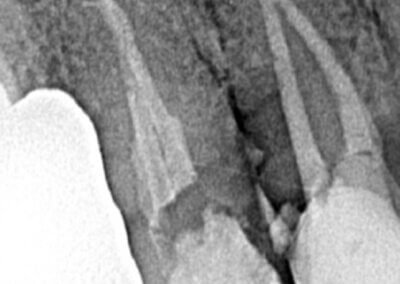

Endodonția este o ramură esențială a stomatologiei, axată pe diagnosticarea, prevenirea și tratamentul afecțiunilor pulpei dentare și a țesuturilor periapicale. Această specialitate joacă un rol crucial în salvarea dinților naturali, evitând extracțiile și menținând sănătatea orală pe termen lung. Prin tehnici avansate și echipamente de ultimă generație, endodonția asigură tratamente precise și eficiente, contribuind la redarea sănătății și funcționalității dinților într-un mod durabil și predictibil.

Tratamentele corecte reduc riscul de infecții și complicații viitoare.